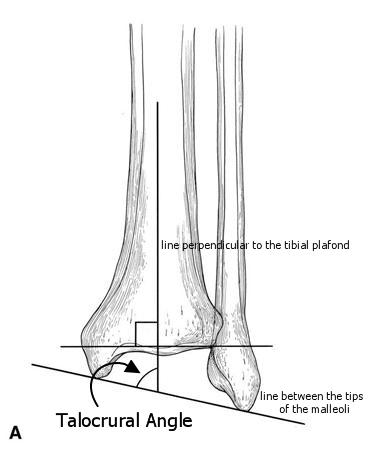

Ankle Fractures